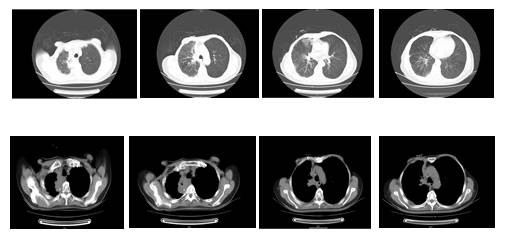

影像检查

PET-CT